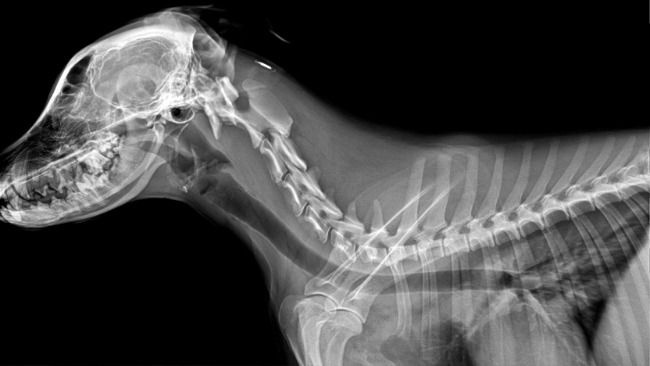

Stefan to kundelek z domieszką beagla. Został adoptowany przez nas rok temu z Krakowskiego schroniska jako szczeniak. To była nasza najlepsza decyzja. Wnosi do naszej rodziny wiele szczęścia. Jest jak nasze 3 dziecko. Kocha ludzi, kocha życie. Jednak mimo młodego wieku już dużo przeszedł. Już w 6 miesiącu swojego życia zaczęła się jego choroba. Stefek z energicznego psiaka w sekundzie stał się apatyczny, miał gorączkę, nie jadł, nie pił, nie wstawał, trząsł się z bólu. Pierwsza diagnoza była powiązana z zapaleniem pęcherza, jednak nie trafna. Niedługo później ataki powróciły. Po wykonaniu mnóstwa badań stwierdzono u niego najprawdopodobniej SRMA steroidozależne zapalenie opon mózgowo-rdzeniowych. Jednak żeby mieć pewność potrzeba jest dalsza diagnostyka w tym tomografia komputerowa i pobranie płynu mózgowo-rdzeniowego. Są to bardzo kosztowne badania, bez których się nie obejdzie.